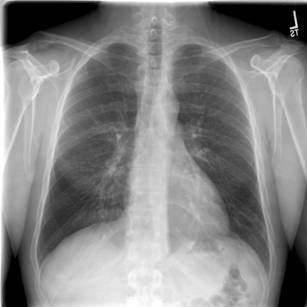

Figure 2: Axial view of high-resolution chest CT using lung windows showing mild central bronchiectasis.